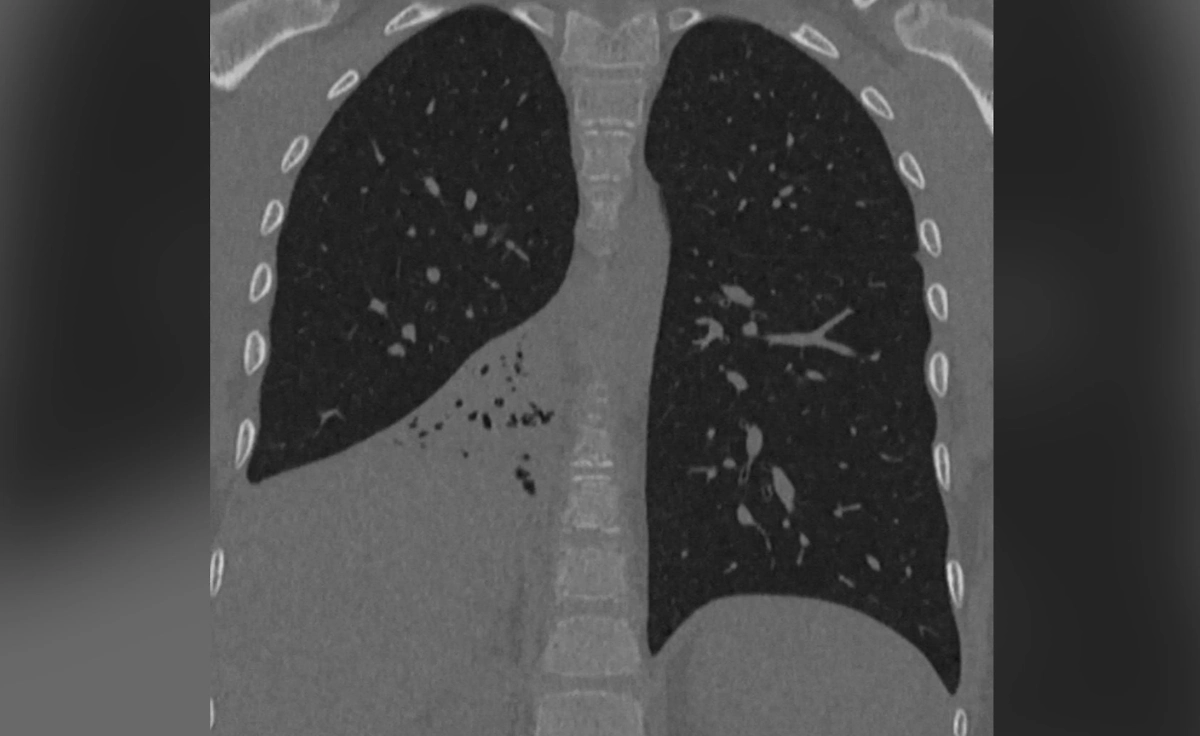

У мальчика в лёгких нашли инородное тело и воспаление. Фото © Предоставлено Life.ru

Ребёнок случайно вдохнул пластиковый колпачок от ручки полгода назад, но не стал рассказывать родителям. Спустя время у мальчика диагностировали затяжную пневмонию, еспираторные инфекции вообще не проходили. Врачи никак не могли понять причину заболевания и списывали всё на слабый иммунитет, пока школьника не доставили в Детский клинический центр им. Л. М. Рошаля. После обследования врачи нашли у маленького пациента нарушение вентиляции и воспалительный процесс в правом лёгком.

«Мы выполнили бронхоскопию, в ходе которой обнаружили пластиковый предмет в бронхах правого лёгкого и выраженное воспаление. С помощью видеоэндоскопического оборудования удалили инородное тело, которым оказался пластиковый колпачок. Со слов мальчика, он случайно его вдохнул», – сказал заведующий хирургическим отделением №2 Никита Степаненко.